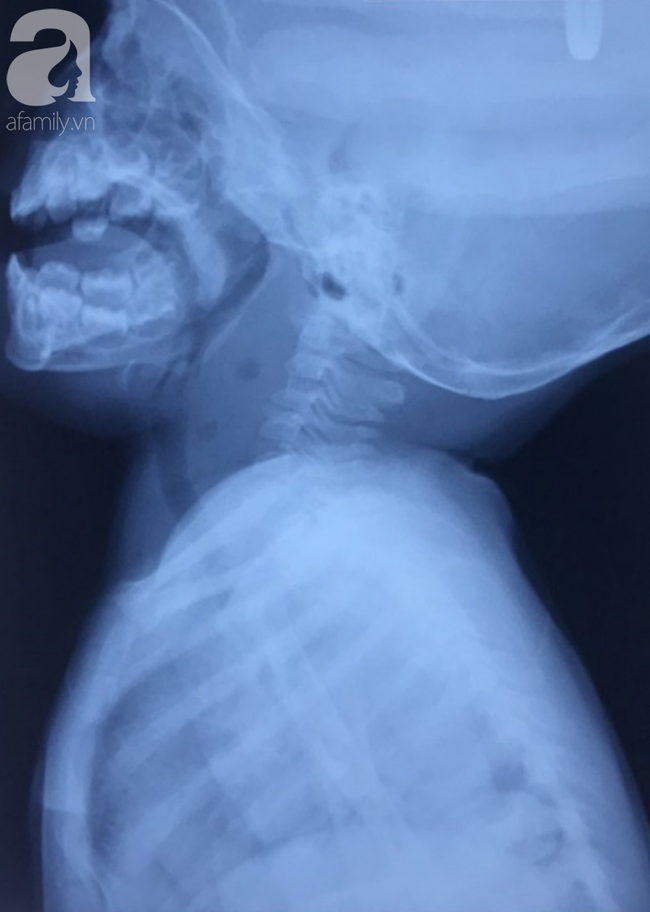

Hình ảnh X-quang và CT -Scan của các ổ áp-xe thành sau họng.

Tại BV Nhi đồng Thành phố, các bác sĩ ghi nhận bé tỉnh, quấy khóc, sốt cao, vùng cổ trái sờ thấy một khối mềm 2x3cm, thành sau họng hơi sưng nề.

Tiến hành xét nghiệm máu khẩn và chụp CT-scan vùng cổ, kíp trực phát hiện bệnh nhân bị nhiễm trùng nặng, có nhiều ổ áp-xe tụ mủ chiếm hơn 2/3 thể tích của vùng cổ.

Ổ áp-xe sinh hơi làm dày khoang thành sau họng.

Quan sát trên hình CT-scan, khối u lan xuống khoang cổ sâu bên trái và nhiều cơ quan nguy hiểm.